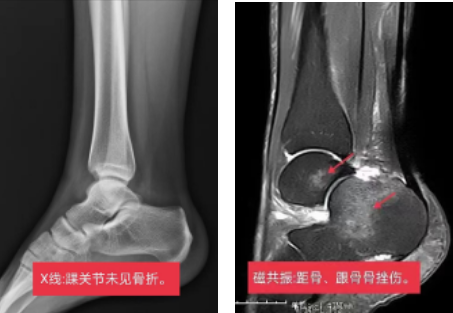

那我们来看看这个病人的情况,X线未见骨折,但是磁共振发现了距骨和跟骨骨挫伤,踝关节腔积液。